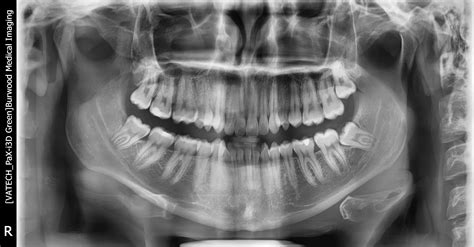

Regular dental check-ups, including digital X-rays, are the only way to monitor the development and positioning of your wisdom teeth. X-rays allow your dentist to see exactly how your teeth are growing beneath the surface, even before they begin to erupt through the gum. Early detection through routine screening allows for proactive planning, rather than waiting for an emergency situation to arise.